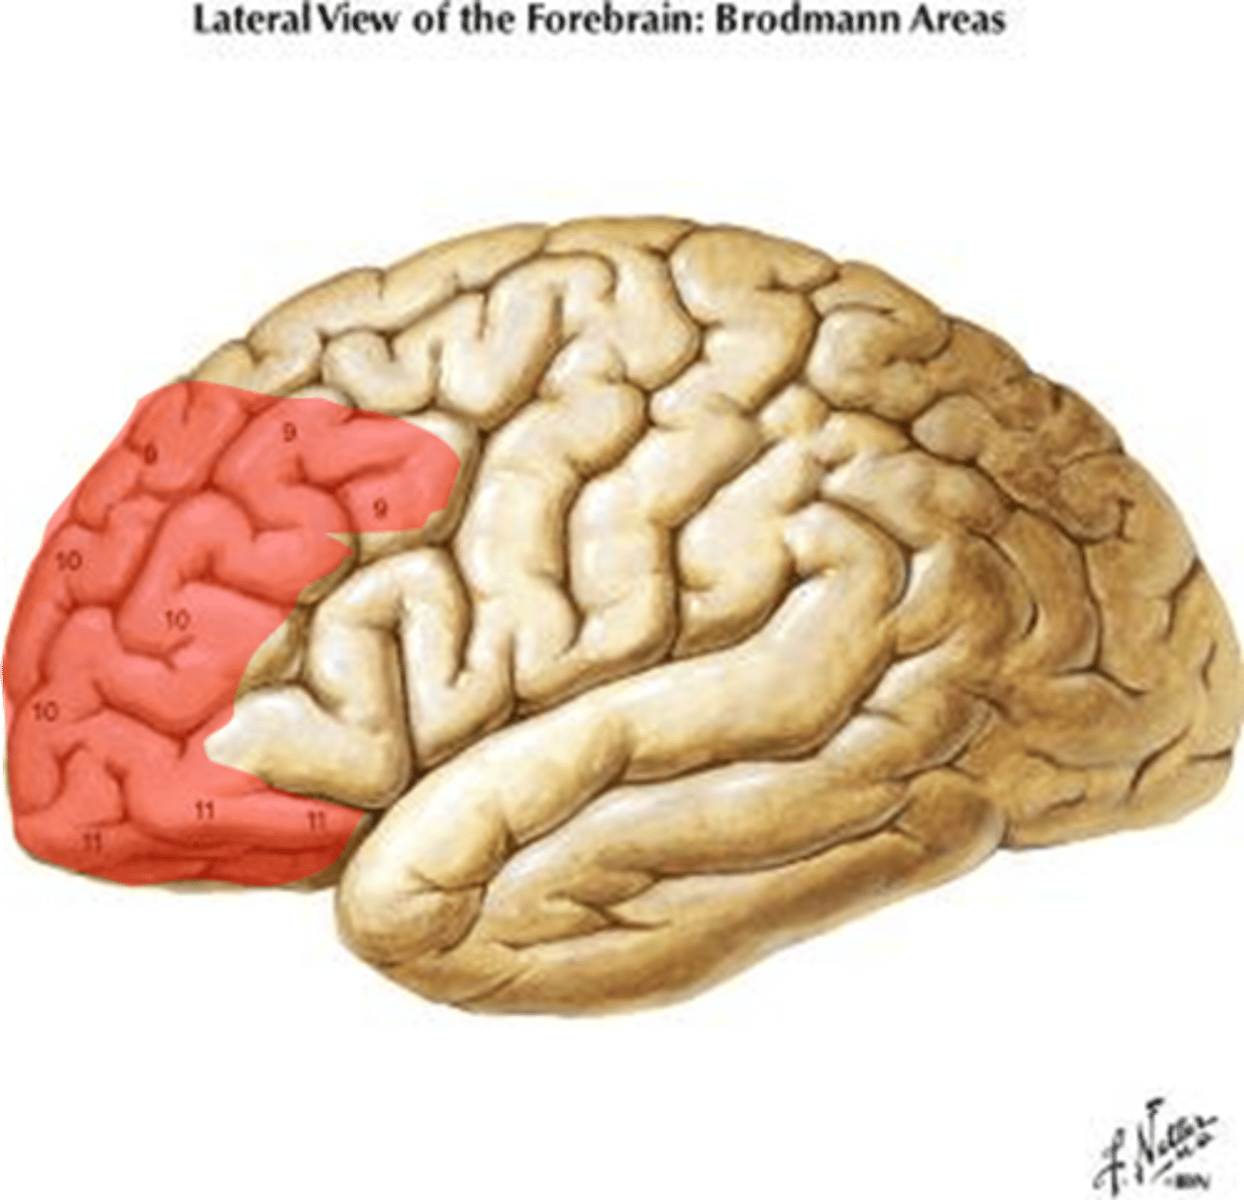

prefrontal cortex

part of frontal lobe responsible for thinking, planning, and language

integrative areas of the cortex

higher cognitive functions; association areas, prefrontal cortex, wernickle's area, broca's area

association areas of cerebral cortex

integrate diverse information

Lobes of the cerebrum

frontal, parietal, temporal, occipital